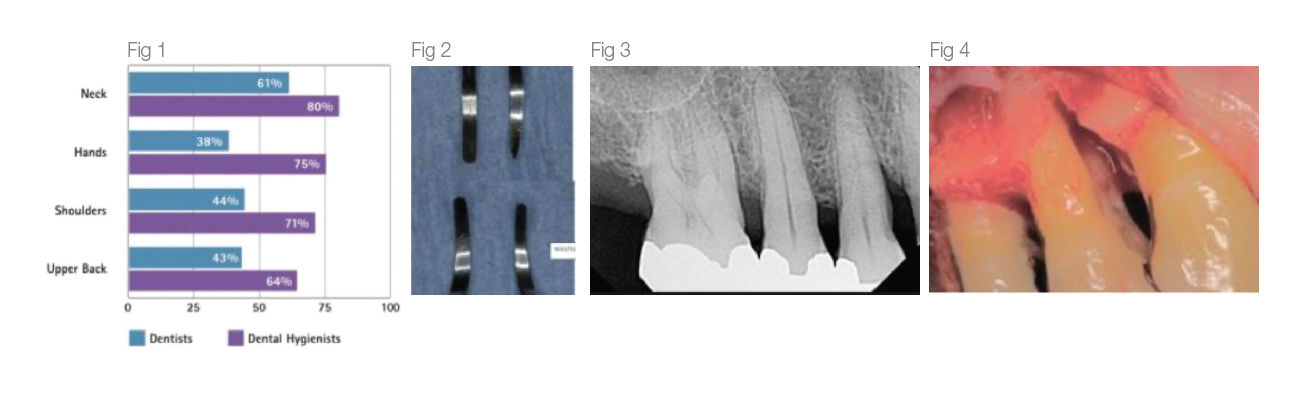

A literature review2 conducted by Johnson and Kanji in 2016 states that 92% of Dental Professionals reported symptoms in at least 1 anatomical, upper body region in the past 12 months with Dental Hygienists being the group most affected (see Fig 1). Work related Musculo- skeletal Disorders (MSD) in dental hygienists are often blamed on repetitive movements, awkward and static postures, pinch- grasp, forceful exertions, vibration, poor ergonomics, and insufficient breaks amongst other factors.

The cost of burnishing calculus, resulting in iatrogenic and supervised progression of periodontal disease when patients are placing their oral health in our hands cannot be measured (Fig 3,4). Breakage of a blade in a patient’s mouth, with possible need for surgical intervention due to using an over-worn working end is a preventable situation with a simple and quick check of the working end against a template.

A routine, quick assessment of your scalers against a template (Fig 2) is a simple way to ensure neither you nor your patients’ health are being compromised and that you can continue to provide care in a safe and healthy environment. This check can be completed by the clinician or nurse prior to instrument processing. Scalers need to be valued as consumable stock to ensure clinicians feel confident and empowered to maintain them without the pressure to try to make them last longer.